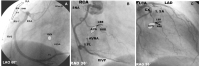

Sinusknoten - AV-Knoten

Abbildung 28: Koronarversorgung des Sinus- und des AV-Knotens (schematisch eingezeichnet). A, links: Der Sinusknoten (SN) wird typischerweise durch den ersten, ganz proximal abgehenden, kräftigen RCA-Vorhofast, der AVN über die vom posterolateralen Ast abgehende AV-Knoten Arterie versorgt (AVNA, LAO 60°, von der Herzspitze her betrachtet). B, Mitte: RAO 30° Projektion der RCA-Anatomie. Koronarversorgung des AV-Knotens und des proximalen His-Purkinje-Systems durch die AVNA. Bei Verschluss der RCA proximal der Abgabe der AVNA sind in der Akutphase AV-Blöcke im AVN häufig. C, rechts: Der erste Septumast der LAD nimmt hauptsächlich an der Versorgung des His-Bündels und der proximalen Tawara-Schenkel teil (RAO 30°). Bei Verschluss dieses Astes oder der LAD proximal davor kann deswegen mit infrahissären Blockierungen und Schenkelblöcken (meistens RSB) gerechnet werden. SN: Sinusknoten, SNA: Sinusknotenarterie, AVN: AV-Knoten, AVNA: AV-Knotenarterie, 1. SA: 1. Septumast des LAD, LBB: linker Tawara-Schenkel, RBB: rechter Tawara-Schenkel, RA: rechter Vorhof, CT: Crista terminalis, RV 1, RV 2: rechtsventrikuläre Äste der RCA, PL: posterolateraler Ast, RIVP: Ramus interventricularis posterior.